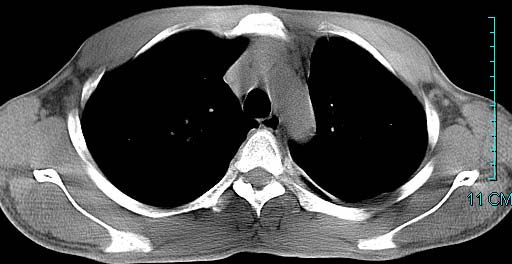

以下是引用ctkz987在2006-3-28 13:04:00的发言:[br]左侧胸腔积液穿刺后多发气液平(多房性),结合临床有高热不除外合并感染。

以下是引用qian在2006-3-28 14:32:00的发言:[br]左肺下叶大片状阴影,密度不均,见有条片影和空洞及气液平,少量胸腔积液伴有胸膜增厚,从图像看积液密度比水的密度高,结合病史,考虑左下肺化脓性炎症伴有脓胸。

以下是引用wawaquan在2006-3-28 22:25:00的发言:[br]左上肺舌段多发斑片影。结合“男24y咳嗽咳痰气促伴高热(38.5--39.5)20多天”及穿刺史,[br]考虑1 左下肺化脓性炎症;2脓胸。

以下是引用乡医在2006-3-28 18:37:00的发言:[br]左侧多发液气平面结合患者男24y咳嗽咳痰气促伴高热(38.5--39.5)20多天,查胸水:ldh239.3,总蛋白59.19,tb-ab阴性,利凡它试验+,红c2.7*109,白c1.08*109,分类淋巴92%分叶8%,考虑1脓胸2肺隔离征感染